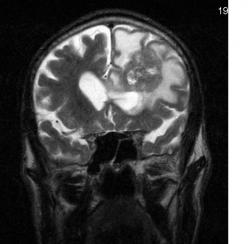

Мужчина 73 лет. За последний год похудел, потерял аппетит. Последний месяц стал плохо ходить, несколько раз падал, неделю назад стал психически не совсем адекватен. Врач - друг семьи, приехавший в гости, настоял на проведении МРТ головного мозга, рентгенографии ОГК и УЗИ брюшной полости. МРТ проводилось в медикаментозном сне, с реанимационным набором наизготовку, по немного укороченным программам. Все закончилось благополучно. Ничего сложного в плане диагностики. Просто не всегда бывает так много и ярко. Есть небольшое продолжение. Потом.

Т2 фронтальные сканы:

метастазы

Да, как ни печально. Еще сделали снимок легких. Справа на верхушке затемнение. Нашли в карточке описание флюорограмм за прошлые годы. Были возрастные изменения, а впрошлом году "на верхушке справа фиброз?". И все. без всяких рекомендаций.